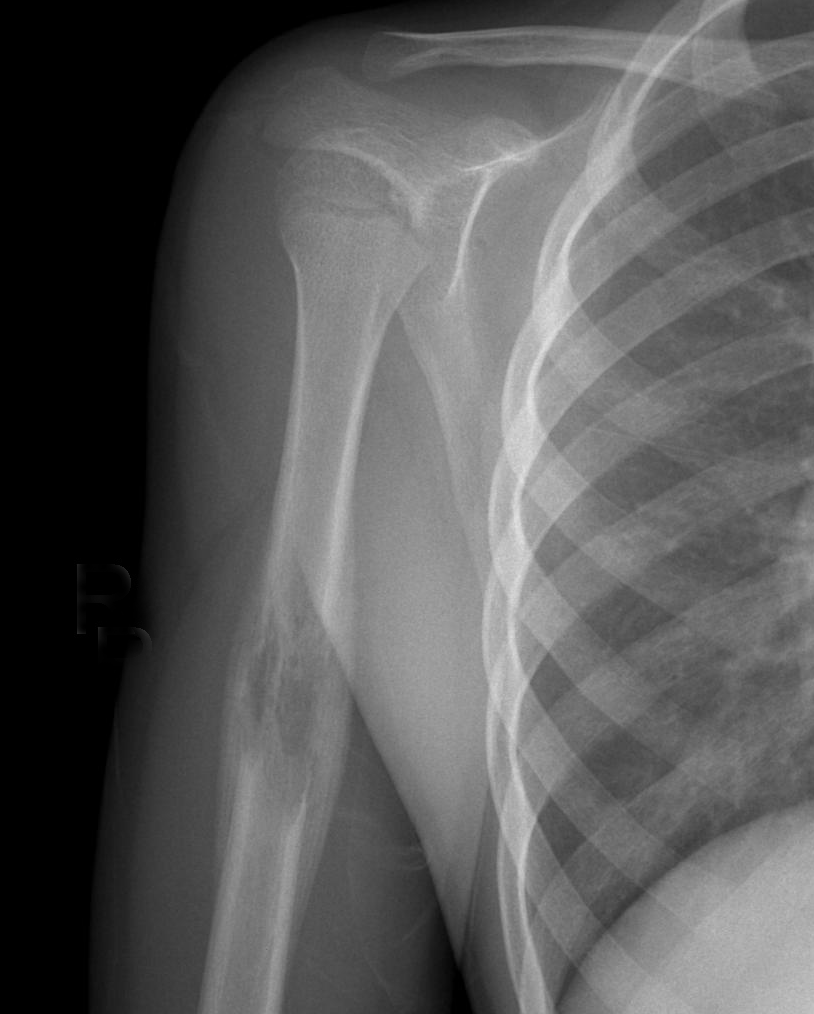

▌侵润性破坏

浸润性骨破坏(图 9、图 10、图 11)是肿瘤组织沿哈弗氏管呈浸润性生长侵蚀骨与骨髓的结果。往往是分化很差、高度间变、异型性明显的肿瘤组织对骨的侵蚀。影像学表现为筛孔样、虫蚀样(皮质骨)、渗透样、斑片状(松质骨)和大片溶骨性破坏,其破坏特点是肿瘤边缘模糊,境界不清,与正常骨无明显界限且有融合成片的倾向。这种不同形态的骨破坏主要是肿瘤对骨侵蚀的程度和部位不同所决定的,不能作为肿瘤定性诊断的依据。

图片

图 9.浸润性破坏:骨肉瘤